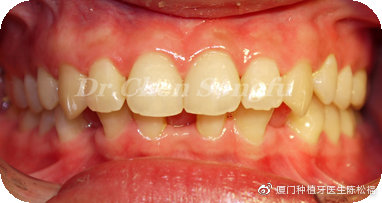

患者情况:E女士,24岁,下前牙先天缺失,存在散在间隙,覆合过深。

检查结果:下前牙从小存在间隙,影响美观。全口牙周情况良好,口腔卫生尚可。32,42缺失,41,31,43,33移位存多处散在间隙。咬合关系基本正常,前牙区深覆合

治疗方案:正畸种植联合治疗-联合治疗才是最佳方案

方案设计:行全口正畸治疗,31,41,33,43前移关闭前牙正中区间隙,预留33,43位置,改善前牙深覆合,33,43各种植一颗植体,完成最终修复。